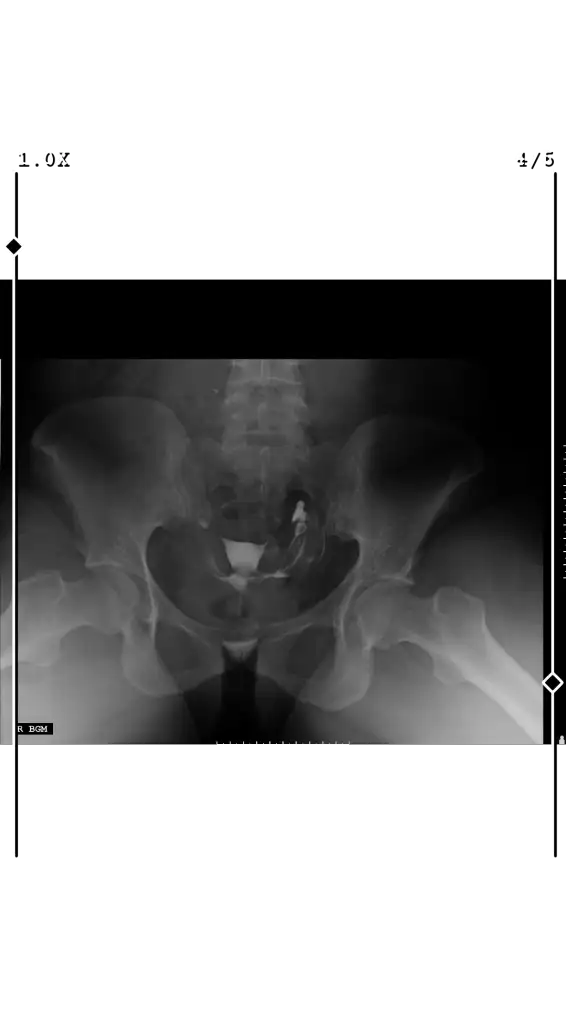

Iyiymiş güzelmiş ama konstrast madde rahimde doluyken olan görüntüyü de görmemiz lazım asimetri var mı diye

Değişik bi açı olmus ama problem yok sanıyorumFilmim bu şekilde

Tüplerin. Açık canım bir tıkanıklık yokmuş kontrast maddes tüplerden geçmiş rahat olabilirsinRahim filmim çekildi

Raporum ;

Uterus kalitesi normal.

Her iki taraf tuval yapilar açık olup, Douglas 'a kontrast madde geçişi izlenmiştir